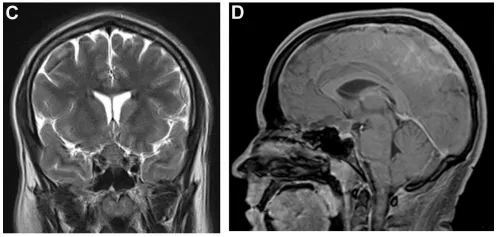

紧接着的CT血管造影排除了血管病变,但随后的MRI检查揭示了一个4厘米大小的非强化斑块样肿瘤,紧紧贴着视交叉,还压迫到了垂体柄和垂体(图1C、1D)。

(C、D)冠状位及矢状位磁共振成像(MRI)提示视交叉旁非强化性、轴外斑块状4cm占位,压迫垂体柄及垂体腺。